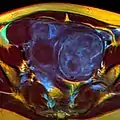

The presence of a uterine fibroid versus an adnexal tumor is made. Fibroids can be mistaken for ovarian neoplasms. An uncommon tumor which may be mistaken for a fibroid is Sarcoma botryoides. It is more common in children and adolescents. Like a fibroid, it can also protrude from the vagina and is distinguished from fibroids.[8] While palpation used in a pelvic examination can typically identify the presence of larger fibroids, gynecologic ultrasonography (ultrasound) has evolved as the standard tool to evaluate the uterus for fibroids. Sonography will depict the fibroids as focal masses with a heterogeneous texture, which usually cause shadowing of the ultrasound beam. The location can be determined and dimensions of the lesion measured. Also, magnetic resonance imaging (MRI) can be used to define the depiction of the size and location of the fibroids within the uterus.